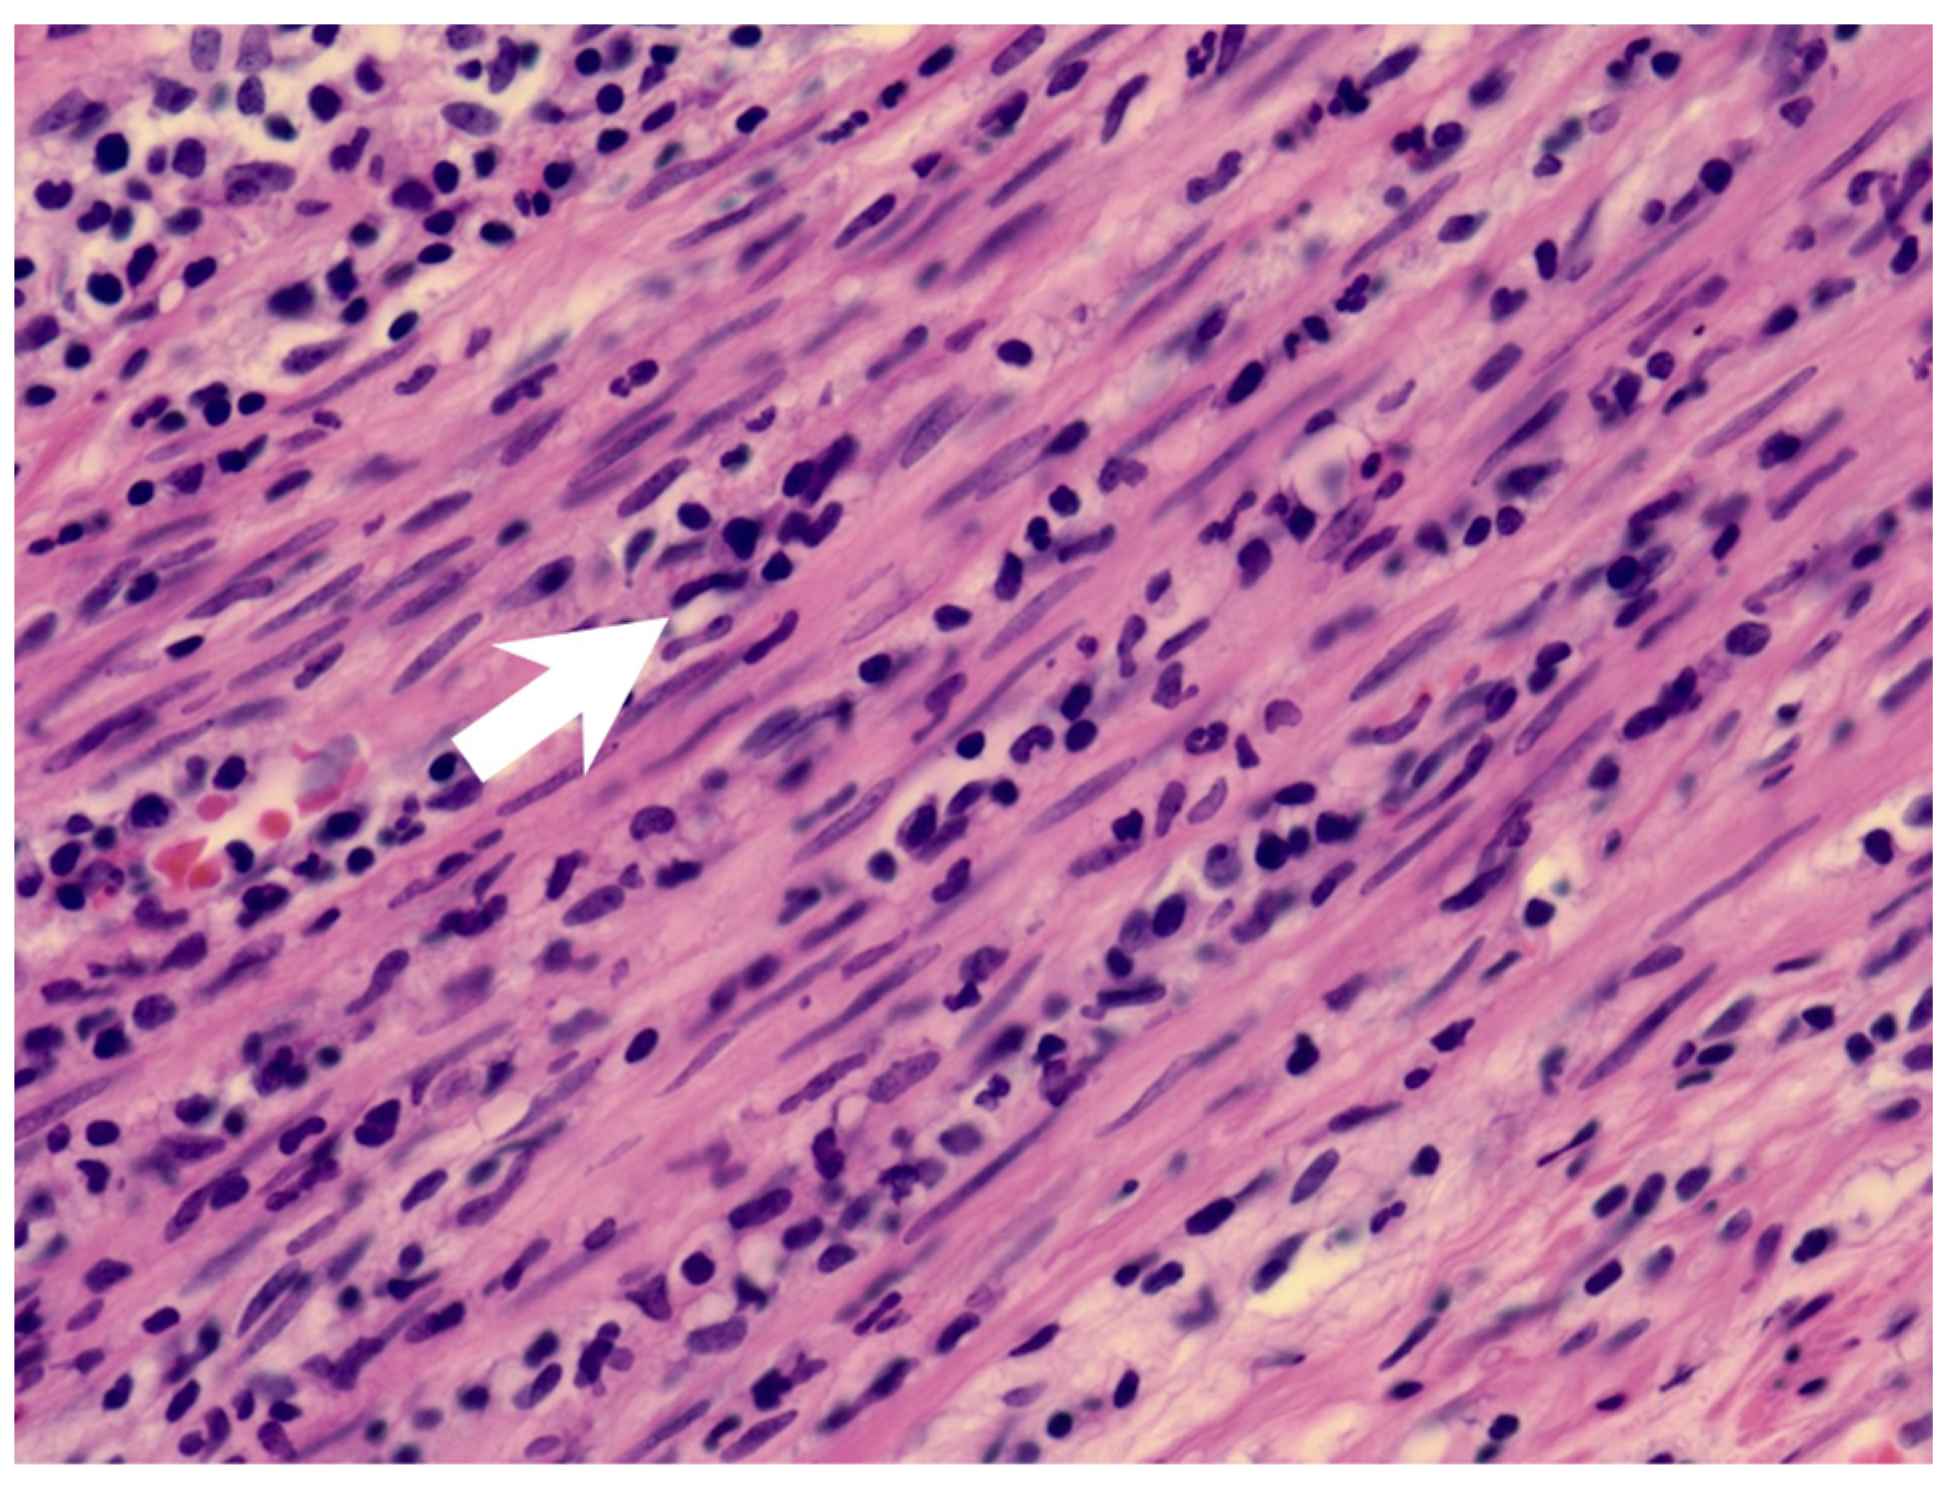

Figure 2.

The muscularis layer of the appendix shows infiltration of acute inflammatory cells (arrow).

KD may present with appendicitis, though it is a rare presentation. There is little information about KDSS with appendicitis. Two possible cases are reported after reviewing the literature (Table 1). Taddio, A. et al. reported a patient with KDSS undergoing a surgical intervention due to a clinical and radiological diagnosis of appendicitis [9]. However, post-operative findings showed thickening of the ileal loops, consistent with mesenteric vasculitis. Gamez-Gonzalez, L.B. et al. reported another possible case [1]. One patient underwent a surgical intervention as a result of a clinical and radiological diagnosis of appendicitis and septic shock. The postoperative findings were positive only for peritoneal cavity effusion. In our case, the clinical diagnosis of appendicitis was made. The pathology report of the appendix showed the presence of neutrophils in the muscularis propria of the appendiceal wall, which was compatible with appendicitis. However, the mucosa of the appendix was intact, which may imply that the inflammatory source was not the appendix.